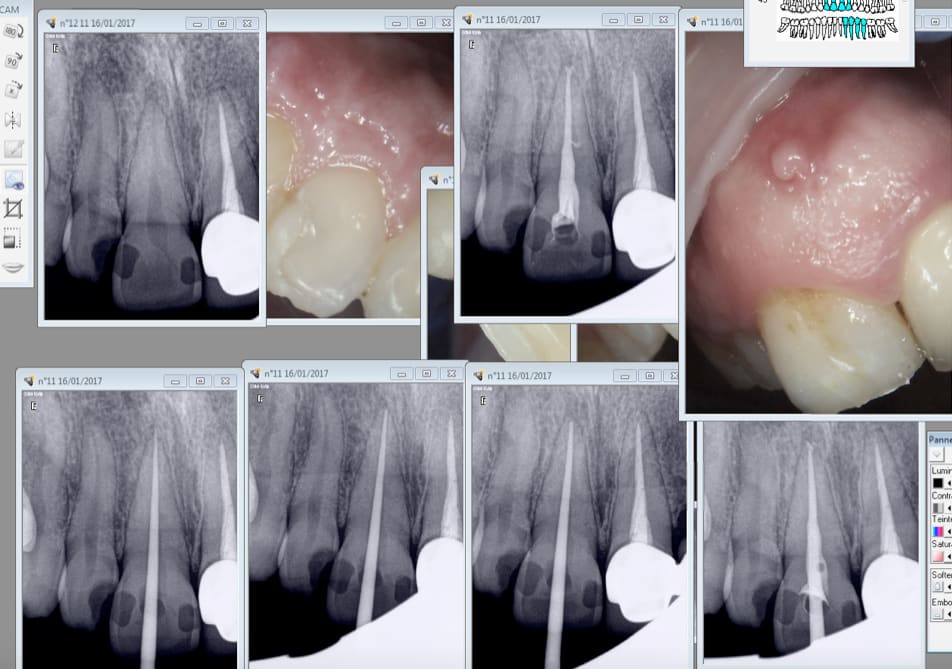

Voici en pièce jointe typiquement les images de dépassements que jai régulièrement. Jai pourtant suivi les instructions du commercial dentsply. Je ne pense pas qu'il s'agisse de gutta étant donné la fine épaisseur... bon je pense que je vais finir pas revenir à la gutta classique ... :/

Img 4453 kwxc1a - Eugenol

bublegum, pour soumettre ton cas, il faut une radio perop, qui aurait montré que tu as beaucoup (beaucoup beaucoup!!!) suralésé .

La ligne blanche apres le depassement le montre. Quelquesoit ta technique d'obturation (a la limite, on s'en fiche!), ne cherche pas ailleurs.

Je ne fais qu'une radio préop avec lime et une postop, je n'ai pas de radio perop.

tu penses que j'ai surtravaillé le canal..? mais poutant j'étais à la bonne longueur d'après la radio cathé et je n'ai eu aucun saignement..

La voilà ! :)

Img 4454 ampdry - Eugenol

Tu jauges ton diamètre apical avec quoi?

Le trait blanc tu es sûr que ce n'est pas ton capteur?

Pour moi, ça manque de conicité apicale, donc le ciment ou la gutta peut plus facilement dépasser par la pression exercée : pas de cône d'arrêt.

J'ai remarqué que c'est principalement sur les dents nécrosées qu'on a ce genre de dépassement : le ciment suit le réseau nerveux.

Je ne pense pas que le suralésage soit la cause ici.

J'utilise depuis longtemps le thermafill et j'ai de temps à autre les mêmes images.

La pression au moment de l'insertion est très importante et même en insérant trèèès lentement on a souvent des dépassement de ciment qui lui est très fluide.